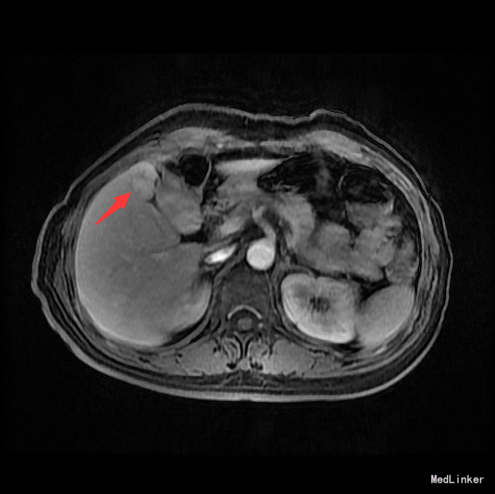

查体:腹平,腹壁静脉无显露,腹软,无压痛,无反跳痛。肝肋下未及。 辅查:AFP 3.43ng/ml, CEA 1.47ng/ml。MR:肝S5段占位性病变(26*25mm),考虑肝癌可能性大,建议活检。

随访:术后病理示:(右肝肿物)送检肝组织部分呈结节状增生,结节间见粗细不等的纤维间隔,其内见血管增生,少量淋巴细胞及浆细胞浸润,符合肝局灶性结节状增生(FNH)。 讨论:肝局灶性结节增生(FNH)是肝内第二常见良性肿瘤,一般无临床症状,影像学表现,MRI上T1WI和T2WI与周围肝实质信号相近,增强扫描动脉期明显强化,若存在中央瘢痕,则中央瘢痕不强化,门脉期及静脉期强化程度减退,中央瘢痕则呈延迟强化。FNH需与肝癌和肝腺瘤鉴别,本例即误诊为肝癌,若存在中央瘢痕,则诊断较容易。